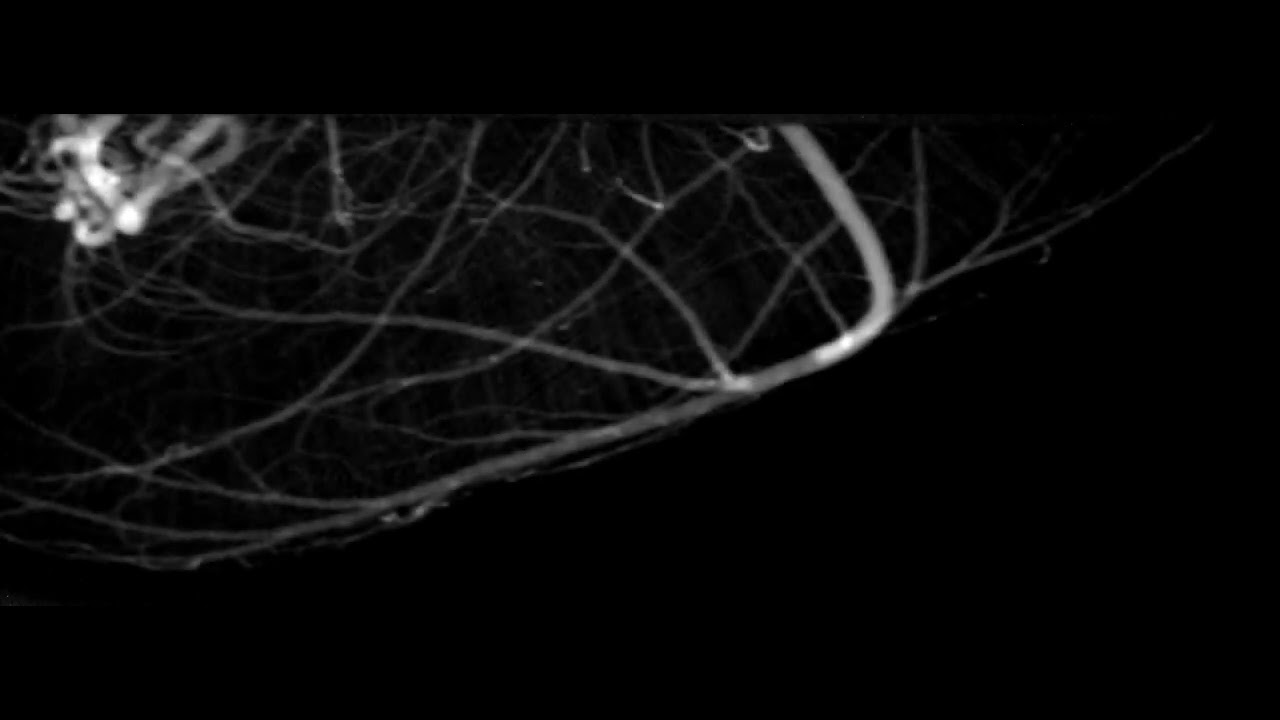

Real-time X-ray imaging of mouse cerebral microvessels

Real-time X-ray imaging of mouse cerebral microvessels in vivo using a pixel temporal averaging method

Rodents are used extensively as animal models for the preclinical investigation of microvascular-related diseases. However, motion artifacts in currently available imaging methods preclude real-time observation of microvessels in vivo. In this paper, a pixel temporal averaging (PTA) method that enables real-time imaging of microvessels in the mouse brain in vivo is described. Experiments using live mice demonstrated that PTA efficiently eliminated motion artifacts and random noise, resulting in significant improvements in contrast-to-noise ratio. The time needed for image reconstruction using PTA with a normal computer was 250 ms, highlighting the capability of the PTA method for real-time angiography. In addition, experiments with less than one-quarter of photon flux in conventional angiography verified that motion artifacts and random noise were suppressed and microvessels were successfully identified using PTA, whereas conventional temporal subtraction and averaging methods were ineffective. Experiments performed with an X-ray tube verified that the PTA method could also be successfully applied to microvessel imaging of the mouse brain using a laboratory X-ray source. In conclusion, the proposed PTA method may facilitate the real-time investigation of cerebral microvascular-related diseases using small animal models.